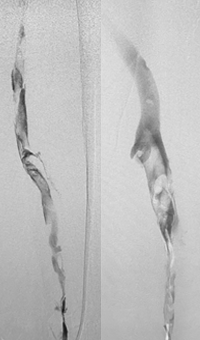

Pharmacomechanical revascularization of extensive iliofemoral thrombus

60 year old female presented with 4 weeks calf pain 1 week swelling.

Procedural steps

• Power Pulse delivery 10mg tPA

• 20 minute dwell time

• ZelanteDVT runtime 415 seconds

• Total case time 90 minutes

Xray of Iliofemoral thrombus pre-treatment and Power Pulse™ delivery

Iliofemoral thrombus pre-treatment (left) and Power Pulse delivery (right)

Xray of veins post-ZelanteDVT mechanical thrombectomy.

Post-ZelanteDVT  Mechanical Thrombectomy

Xray of veins post-ZelanteDVT runtime 415 seconds.

Post-ZelanteDVT runtime 415 seconds

Images Courtesy of Charles Wyble M.D. – Vascular Surgical Associates, Marietta, Georgia – January 5, 2016